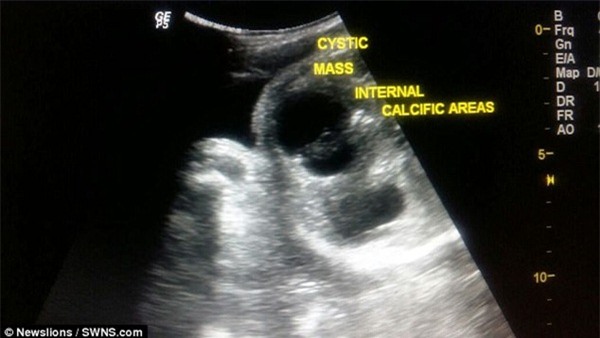

Hình ảnh chụp chiếu cho thấy ổ bụng của bé xuất hiện một thai nhi ký sinh.

Bác sĩ Bhavna Thorat cho biết: "Phần thai phụ ký sinh đó nó nằm trong bụng của bé sơ sinh, tôi có thể nhìn thấy chi trên và chi dưới của thai nhi, một cái đầu có bộ não bên trong. Tuy nhiên, cơ thể bé sơ sinh ký sinh này không có xương sọ".

Phần thai nhi ký sinh có não bộ, tay và chân.